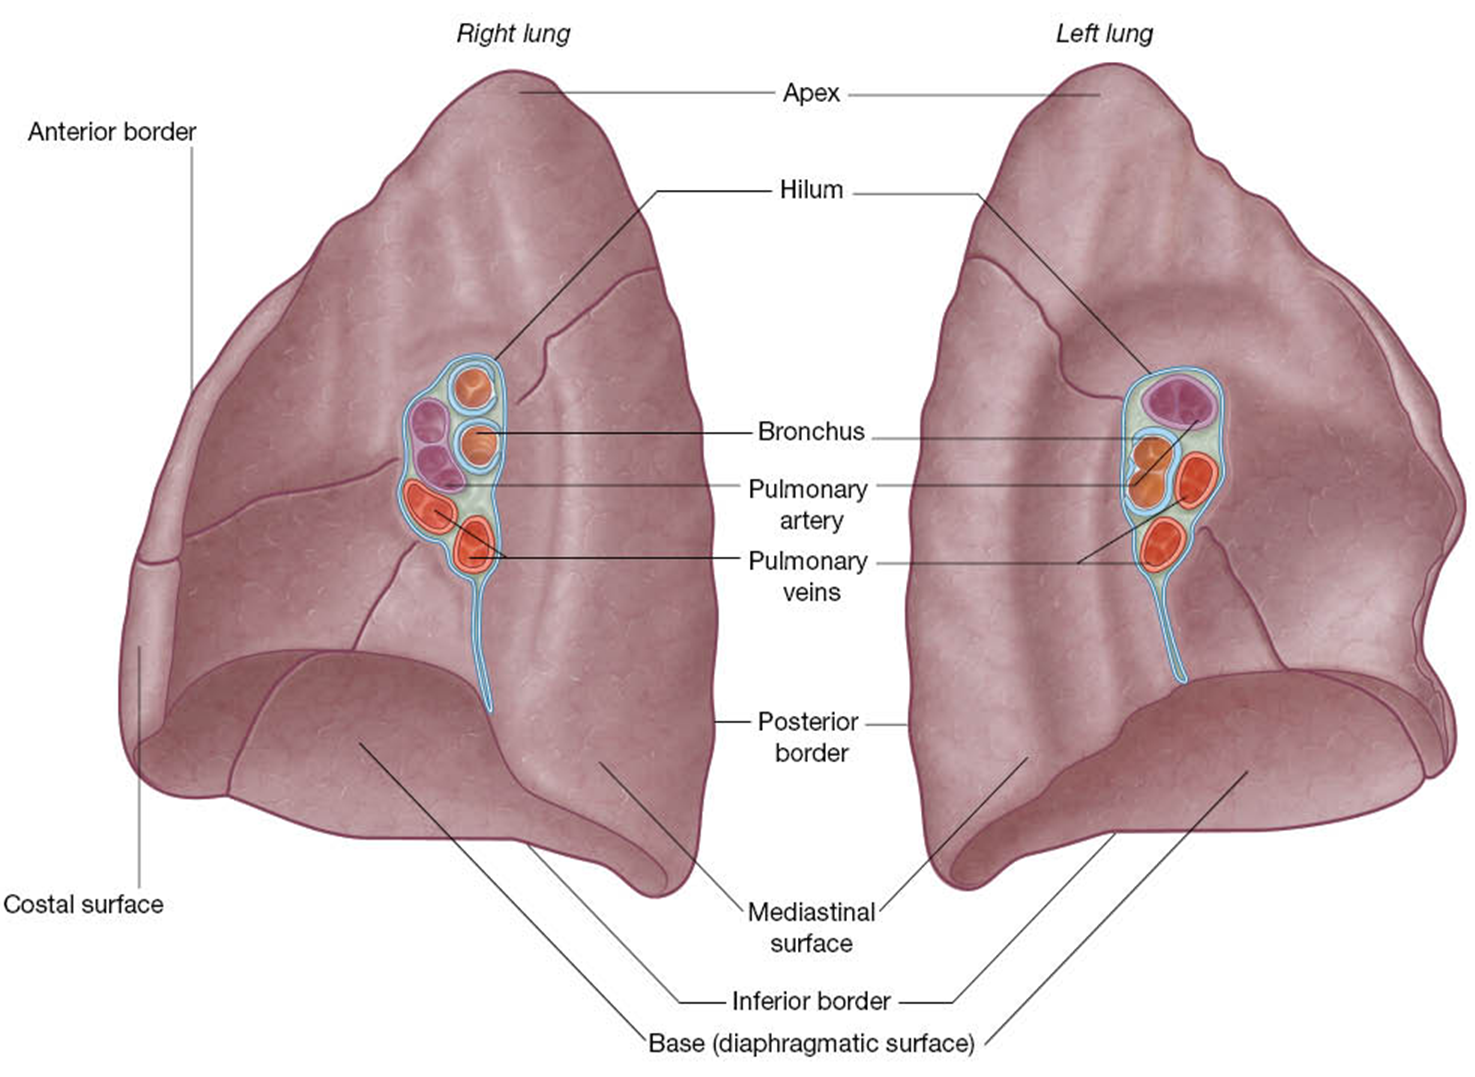

lung basics

2 lungs.

Organs of respiration on either side of the mediastinum.

Surrounded by pleural cavities.

Air enters and leaves via main bronchi.

Apex projects above 1st rib.

Base sits on diaphragm.

Costal and mediastinal surfaces.

Borders: anterior, posterior, and inferior.

Root of the lung enters at the hilum

R lung mediastinal surface

The root of the lung is made up of the bronchi & pulmonary vessels. These structures enter and exit at the hilum of the lung.

The pulmonary ligament, double layer of pleura, permits movement during respiration.

The grooves and impressions shown on the cadaver lung illustration are artifacts of embalming. They demonstrate important relationships.

At the hilum of the right lung, the bronchus to the superior lobe has branched from the main bronchus and thus it is superior to the pulmonary artery.

The combined bronchus to the middle and inferior together is inferior to the pulmonary artery.

The pulmonary veins are most inferior.

L lung mediastinal surface

On the left lung, the main bronchus is inferior to the pulmonary artery.

The veins are anterior and inferior to the other structures.

Bronchial vessels can also be seen.

Notice the arrangement of the vessels and bronchi at the root of the lungs.

Note the lung borders and surfaces.